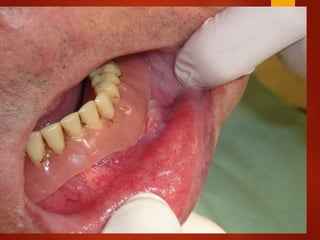

El documento es un registro médico odontológico que muestra las fechas de las visitas de un paciente al centro de salud El Raval, incluyendo exámenes y tratamientos realizados como la extracción de cálculos salivales en abril y mayo de 2012.